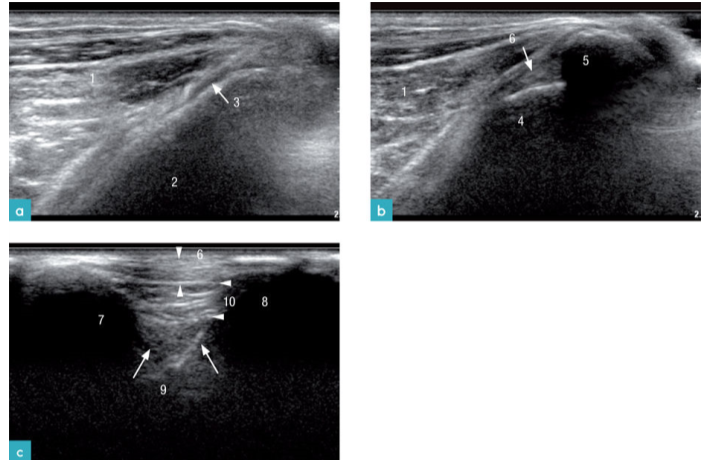

浅表软组织的影像表现根据所处位置的功能,动物的体况及水合状态不同而有所变化。皮肤分为表皮,真皮、皮下组织(图6)。皮下组织由脂肪和结缔组织构成,其回声特点为混合回声内含有高回声亮线。脂肪与腹壁,胸壁,骨骼肌相连。扫查软组织时,还可观察到其他周边结构,如骨骼,肌肉,腺体,淋巴结,血管以及神经。

非泌乳期乳腺组织的超声影像为质地均一的低回声组织,厚度约为2mm。处于妊娠期的乳腺影像,其回声增强且颗粒感明显,泌乳期的乳腺回声最高(图7)。妊娠后期乳腺可增至6-9mm厚。泌乳期的乳腺厚度与幼猫吮吸刺激的程度有关,刺激越强厚度越大,最厚可达11mm。只有在妊娠末期以及泌乳期才可观察到乳腺中的导管。